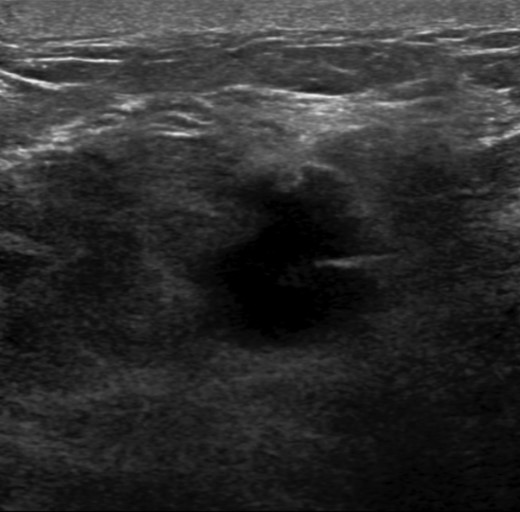

The patient is a 47-year-old Polish premenopausal female who presented with complaints of a non-tender palpable left breast mass for 4 months at an outside institution. She underwent a diagnostic mammogram and ultrasound that reported a 2-cm irregular, hypoechoic mass at 12 o'clock. The mass had indistinct borders on ultrasound (Figs. 1,2). Bilateral breast MRI revealed no disease in either axilla or the right breast. There was a 2.2-cm enhancing mass in the left breast at 12:00 that was consistent with the patient's biopsy-proven malignancy (Fig. 3). Upon examination in the Breast Surgery clinic, she underwent a core needle biopsy, which revealed a poorly differentiated triple-negative invasive ductal carcinoma (Fig. 4).

Left breast ultrasound. There is a 1.9 × 1.4 cm irregular mass in the left breast at 11–12:00 6 cm from the nipple.